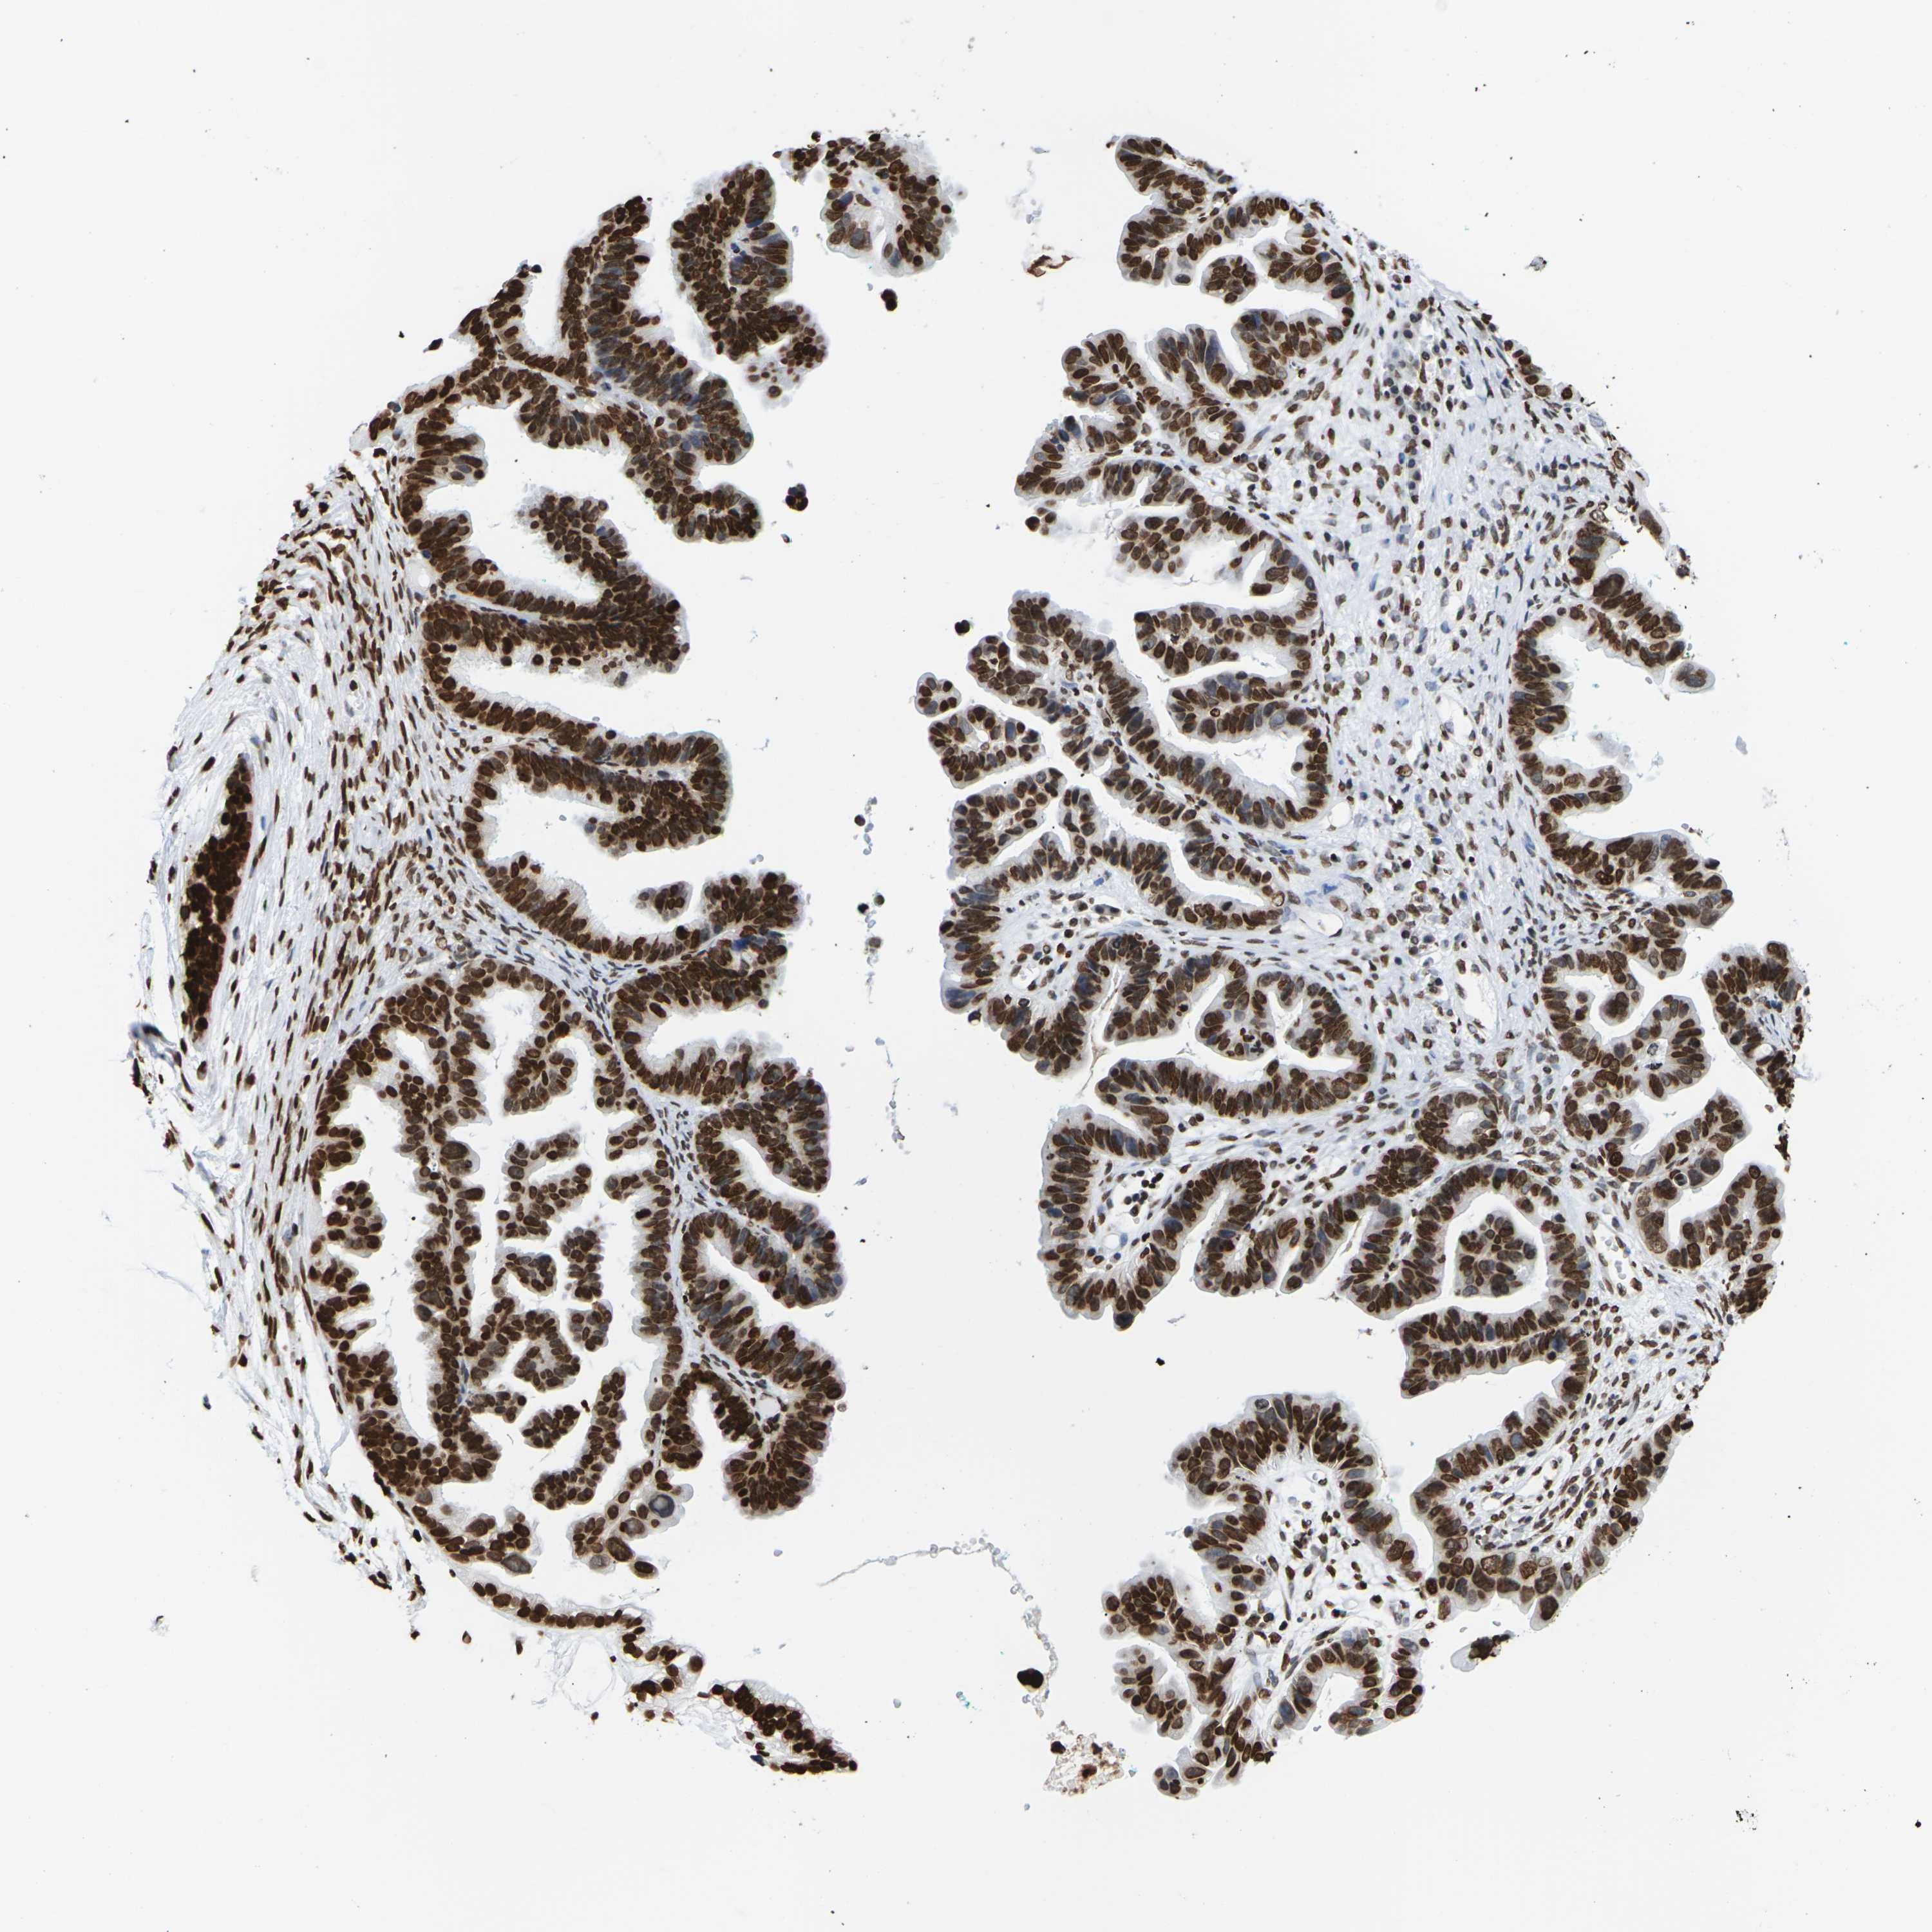

OVARIAN CANCER - Protein expressioni

A mouse-over function shows sample information and annotation data. Click on an image to view it in a full screen mode. Samples can be filtered based on level of antibody staining by selecting one or several of the following categories: high, medium, low and not detected. The assay and annotation is described here.

Note that samples used for immunohistochemistry by the Human Protein Atlas do not correspond to samples in the TCGA dataset.

Antibody stainingi

Antibody staining in the annotated cell types in the current human tissue is reported as not detected, low, medium, or high, based on conventional immunohistochemistry profiling in selected tissues. This score is based on the combination of the staining intensity and fraction of stained cells.

Each image is clickable and will lead to virtual microscopy that enables deeper exploration of all samples and also displays staining intensity scores, fraction scores and subcellular localization as well as patient and tissue information for each sample.

Antibody HPA041189

Antibody CAB011483

Cystadenocarcinoma, serous, NOS

Carcinoma, endometroid

Cystadenocarcinoma, mucinous, NOS

Carcinoma, NOS